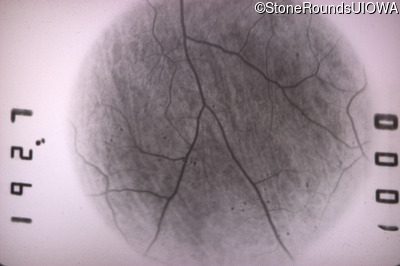

Fluorescein Angiography - Right - 20/25 +2 sc

Exemplar